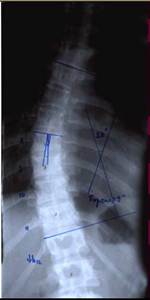

До сих пор в ортопедии принято множество методик измерения угла искривления позвоночника, и, соответственно, множество различных классификаций с разными величинами углов в градусах. Измеряется искривление так: на рентгенограмме надо провести несколько прямых линий между позвонками, а затем измерить углы между ними. В нашей стране наиболее распространена классификация, предложенная В.Д. Чаклиным. В иностранных научных источниках чаще приводится метод Дж. Кобба. Суть его заключается в следующем: на рентгеновском снимке позвоночника врач измеряет S-образное двойное искривление. В верхнем участке искривления с помощью линейки проводят две горизонтальные линии: одна над верхним позвонком, от которого идет кривизна, другая - над нижним. Если провести еще две линии, идущие перпендикулярно первым, образуется угол. Его и измеряют в градусах

Как видно, принцип измерения как у русского, так и американского профессора практически одинаковый. Разница в том, что по Чаклину, чем больше градусов, тем легче степень болезни, а по Коббу - наоборот.

Классификация выраженности сколиоза по В.Д. Чаклину (слева), по Лж. Коббу (справа) Степени тяжести сколиоза (углы искривления позвоночника, в градусах) Графический расчет на рентгенограмме: а - I степень; б - II степень; в - III степень; г - IV степень.

По В.Д. Чаклину

По Дж. Коббу

I степень 180 - 175 меньше 15

II степень 175-155 20-40

III степень 155-100 40-60

IV степень меньше 100 больше 60

Нами проведен анализ 209 случаев оперативного лечения сколиотической деформации II - IV степени с использованием двухпластинчатого эндокорректора с многоуровневой фиксацией. Срок наблюдения составил от 1 до 4-5 лет с наличием корректора и от 1 до 3 лет после его удаления. Средний возраст 13,8 года. Врожденный сколиоз был только в 3,83% случаев. Деформация с наименьшим углом по Коббу составила 21°, с наибольшим 124°. Основное число прооперированных больных было с углом искривления в диапазоне 31°-70°. Среди них у 43% угол искривления составил 51°- 60°.

При сколиозе IV степени с углом деформации в диапазоне от 51° до 70° коррекция составила от 79,2 до 84,8%. С углом от 71° дог 80° - 73,3 - 86,5%. С искривлением от 81° до 122° удалось достигнуть одномоментно коррекции в пределах 72,7 - 73,8%.

Больная Л-ч, 12 лет сколиоз IV степени  Результат оперативного лечения